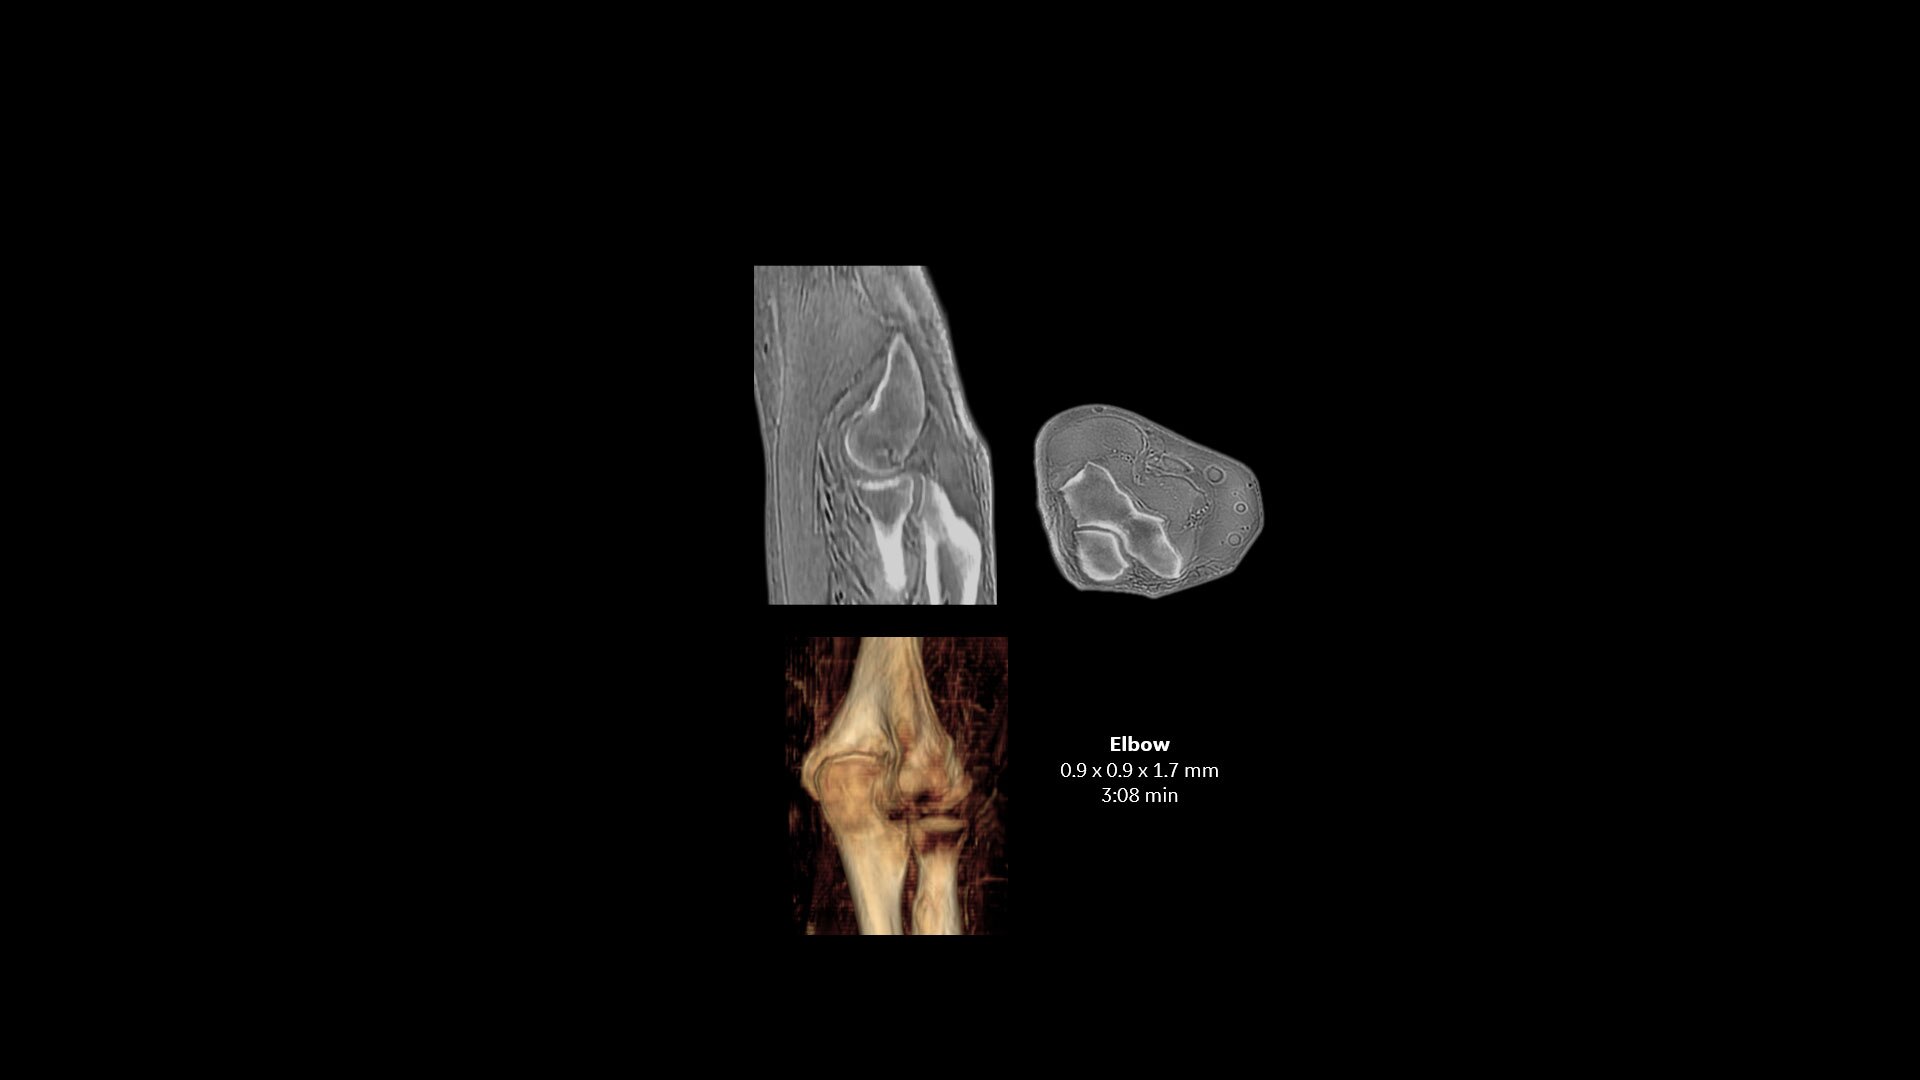

Available for all anatomies without ionizing radiation, oZTEo delivers images of bone morphology, calcification, ossification and fractures. oZTEo complements conventional MR soft tissue exams with perfect co-registration and provides 3D isotropic imaging using a radial ZTE acquisition, with inherent motion insensitivity. Use oZTEo with Volume Illumination for realistic 3D rendering.

Geometric measurement with oZTEo

oZTEo images can be used for geometric and morphologic measurements, such as in routine FAI in the hip.  These results have been published in The American Journal of Sports Medicine, 2019: 47(14):  3460-3468.